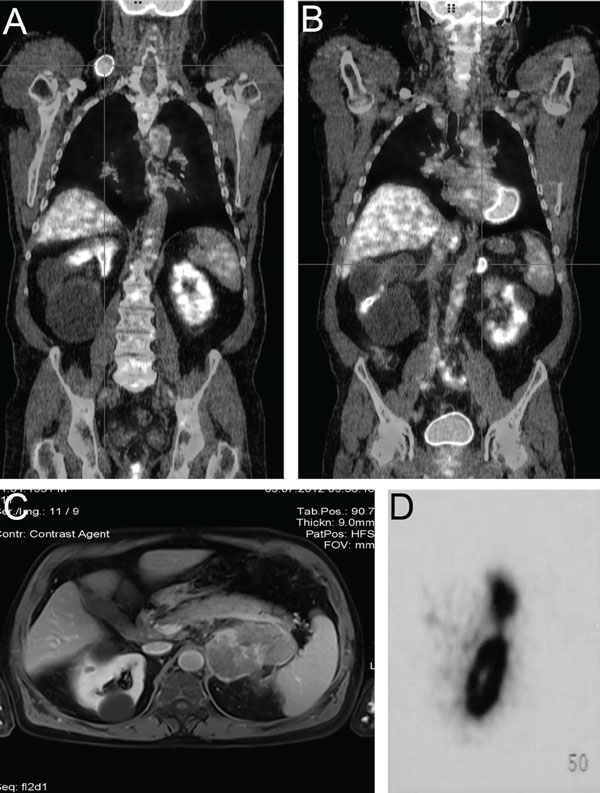

A 61-year-old male farmer was referred for evaluation of a mass in the right supraclavicular region and a left adrenal lesion. There was nothing noteworthy in the patient’s family medical history. The patient had a history of total thyroidectomy with central and right lateral cervical lymph node dissection three years previously. The histopathological examination was positive for medullary carcinoma and multifocal papillary thyroid carcinoma, both metastatic to regional lymph nodes. He had received radioiodine ablation therapy and was under thyroxin suppression therapy. Further imaging studies were negative. Genetic testing for RET proto-oncogene mutation revealed a common polymorphism in exon (c.2071 G>A/p.G691S) and a synonymous variation in exon 15 (c.2712 C>G/p.S904S). During follow-up, due to the neck swelling, he underwent a neck ultrasound and a 2-(18F) fluoro-2-deoxy-D-glucose positron emission tomography/computed tomography (18F-FDG PET/CT). The ultrasound revealed a solid hypoechoic mass measuring 5cm in the right supraclavicular region, identified as lymph nodes. The 18-FDG-PET/CT revealed a significant tracer uptake in the right supraclavicular region, the anterior upper mediastinum and the left adrenal gland (Figures 1A & 1B).

Figure 1. A) 18F-FDG PET/CT: significant tracer uptake in the right supraclavicular region (SUVmax: 10.0). B) Significant tracer uptake in the left adrenal grand (SUVmax: 4.7). C) MRI: large solid mass 88.5 min in diameter of the left adrenal gland, with inhomogeneous enhancement of the contrast agent and a low diffusion rate. D) OctreoScan: increased trace uptake in the left adrenal gland.

A computed tomography (CT) scan of the chest confirmed the block of lymph nodes measuring 5.5cm in the right supraclavicular area and a large, solid, inhomogeneous mass in the left adrenal gland. Magnetic resonance imaging (MRI) of the abdomen revealed a solid left adrenal mass measuring 88.5mm, with inhomogeneous contrast enhancement agent and a low diffusion rate (Figure 1C). The mass was identified as a pheochromocytoma. In 111-Pentetreotide (OctreoScan) scintigraphy demonstrated a significantly increased tracer uptake in the right supraclavicular region, the anterior upper mediastinum and the left adrenal gland (Figure 1D). The CT scan of the chest did not show the mass to be in the anterior upper mediastinum as seen on OctreoScan. However, meta-iodo-benzyl-guanidine (I131 MIBG) scintigraphy was negative.

The differential diagnosis between benign and malignant lesions of the adrenal glands is not always easy. FDG-PET/CT provides both anatomical and functional information and the maximum standardized uptake value (SUVmax) is the best index to assess disease activity. An SUVmax cut-off value of 4.2 corresponds to a sensitivity of 88.6% and specificity of 88.2% in detecting malignant adrenal lesions.33 Notably, our patient had an SUVmax of 4.7 in his adrenal mass, suggesting the presence of malignancy.